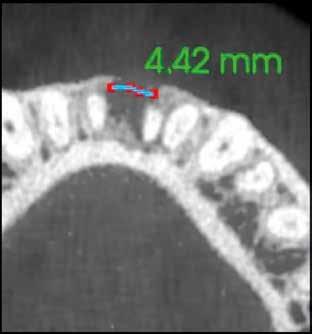

A radiológiai felvételek elemzése során a fog gyökércsúcsának megfelelően radiolucens elváltozást észleltünk, valamint a fognyak területének megfelelően szintén egy radiolucens területet figyelhettünk meg (1–2. ábra). Az elváltozások kiterjedésének és mélységének pontosabb meghatározása érdekében CBCT-felvétel készült (3. ábra). A felvétel alapján Heithersay-féle III. osztályú külső fognyaki gyökérfelszívódást diagnosztizáltunk (Heithersay Class III external cervical invasive root resorption; ECIR). Ezzel egyidejűleg pedig szimptomatikus periapikális periodontitis is fennállt. Ezt követően a pácienst a vizsgálati eredményekről, a kezelési alternatívákról és a várható prognózisról is tájékoztattuk.

A CBCT-felvételek rendkívül hasznos információkkal szolgálhatnak az endodonciai kezelések során. A felvételek segítségével meghatározhatjuk a külső fognyaki rezorptív lézió kiterjedését, felismerhetjük és osztályba sorolhatjuk az esetleges periapikális elváltozásokat, valamint nagyobb pontossággal felmérhetjük a fog belső anatómiai felépítését. Több szerző egymástól függetlenül is igazolta, hogy a CBCT rendkívül hasznos eszköz a rezorptív léziók diagnosztizálása során.

3. a–d ábra: A koronális síkú metszeten jól megfigyelhető a lézió mesio-distalis kiterjedése (a), a szaggitális síkú metszet a lézió vesztibulo-orális nagyságát mutatja (b), a gyökércsúcs körül elhelyezkedő lézió a 3 dimenziós rekonstrukciós képen és a mesio-disztális irányú metszeten is jól megfigyelhető (c–d).

A cikkekben bemutatott esetnél a kezelésre szoruló fog gyökércsúcsánál periapikális lézió volt megfigyelhető és ezzel egyidejűleg külső fognyaki gyökérrezorpció is fennállt. A periapikális és a rezorptív lézió méretének pontos meghatározását és térbeli elhelyezkedésének vizsgálatát CBCT-felvétel segítségével végeztük.